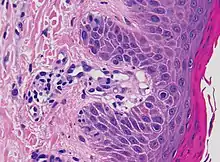

Interface dermatitis with lichenoid inflammation

| Generally/Not otherwise specified | Typical findings:[2]

| Lichen planus | Irregular epidermal hyperplasia with a jagged “sawtooth” appearance, compact hyperkeratosis or orthokeratosis, foci of wedge-shaped hypergranulosis, basilar vacuolar degeneration, slight spongiosis in the spinous layer, and squamatization. The dermal papillae between the elongated rete ridges are frequently dome shaped. Necrotic keratinocytes can be observed in the basal layer of the epidermis and at the dermal-epidermal junction. Eosinophilic remnants of anucleate apoptotic basal cells may also be found in the dermis and are referred to as “colloid or civatte bodies”. Whickham striae are usually seen in the areas of hypergranulosis. Vacuolar degeneration at the basal layer may be noted leading to focal subepidermal clefts (Max Joseph spaces). Squamatization occurs as a result of maturation and flattening of cells in the basal layer. It happens in areas of marked hypergranulosis with prominence of the sawtooth pattern of rete ridges. Wedge-shaped hypergranulosis can occur in the eccrine ducts (acrosyringia) or hair follicles (acrotrichia). In the hypertrophic subtype, the associated hyperkeratosis, parakeratosis, hypergranulosis, papillomatosis, acanthosis, and hyperplasia markedly increased with thicker collagen bundles forming in the dermis. Moreover, the rete ridges are more elongated and rounded as opposed to the typical sawtooth pattern. In atrophic LP, loss of the rete ridges and dermal fibrosis is prominent. In vesiculobullous LP, the disease progression is quicker. Hence, some of the distinctive features such as hyperkeratosis, hypergranulosis, or dense lymphocytic dermal-epidermal infiltrate may not be present. LP lesion may resolve with residual hyperpigmentation caused by a persistent increase in the number of melanophages in the papillary dermis.[9] | ![]() | ![]() |